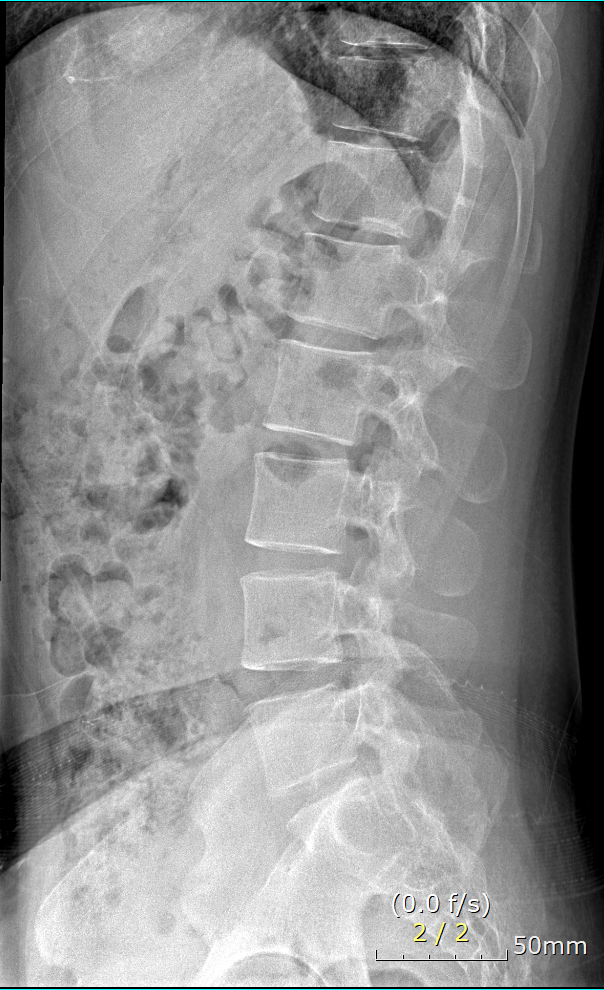

mri 판독 결과 남깁니다..

Clinical information: back pain

T12-L1 level에서 disc가 뒤쪽 Lt. central aspect로 protrusion되어 있고 mild한 dural sac indentation을 주고 있음.

그 외 disc level과 neural foramen에서 definite한 abnormality는 보이지 않음.

Vertebral body의 SI, shape, 그리고 alignment도 정상이며, scanned TL-spinal cord내에 definite한 abnormal signal intensity는 보이지 않음.

• 1번 째 사진

아래 사진에 있는 부위가 아마 T12/L1 사이에 디스크가 살짝 뒤로 빠져있다는 부위이실겁니다.

옆에서 보면 두번째 사진이구요.